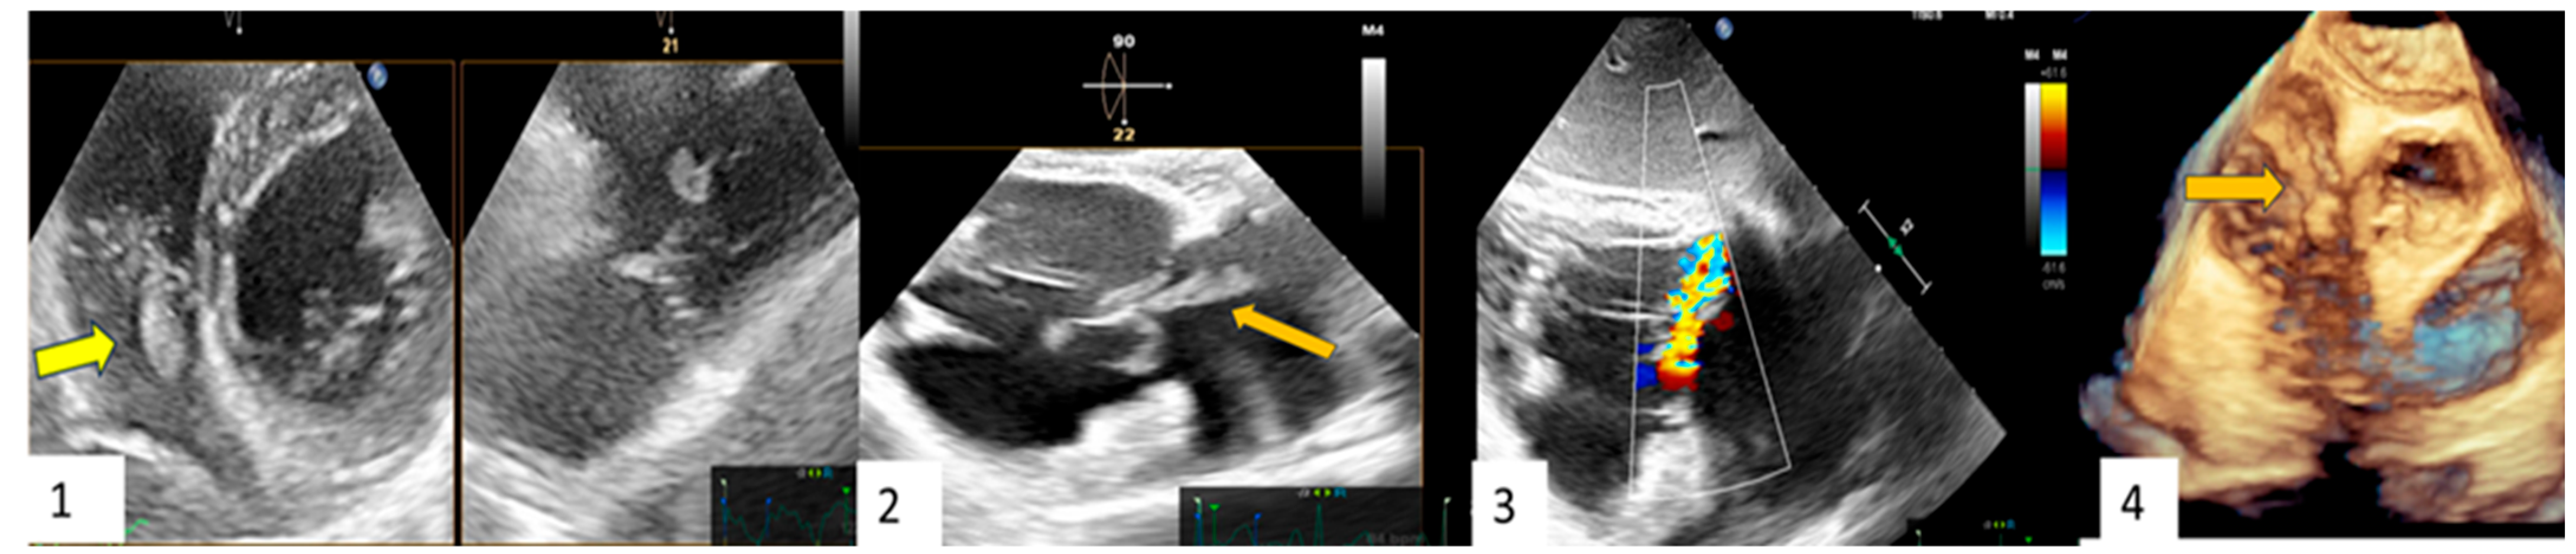

| Clinical Case 1. A 38-year-old woman without pre-existing cardiac disease was admitted for 10-day mild fever associated with progressive epigastric pain and vomit one month following piercing implant. Clinical examination revealed a painful hepato-splenomegaly. Cardiovascular evaluation showed tachycardia (120 beat/min), arterial hypotension (75/45 mm Hg) without any cardiac murmur. Abdomen echo scan confirmed a normally structured hepatosplenomegaly, together with inferior vena cava enlargement suggesting venous congestion. Blood chemistry showed increased white cell count (12,860) and severe anemia (Hb3.9), requiring urgent transfusion. C-reactive protein was moderately high (16.5). Blood culture was positive for methicillin sensitive S. aureus. TT (1) and subsequent TEE (2,3,4) showed a large iso-echogenic vegetation (yellow arrow), which was attached to the atrial surface of the anterior leaflet of the tricuspid valve, prolapsing into the right atrium during the systole and determining related severe valve regurgitation. The patient underwent culture-guided antibiotic therapy with disappearance of the vegetation and reduction in tricuspid regurgitation to a moderate degree at subsequent echocardiographic examination.  |